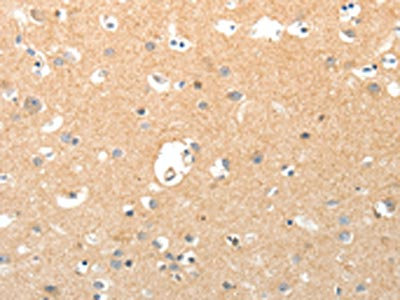

The image on the left is immunohistochemistry of paraffin-embedded Human brain tissue using CSB-PA976408(TNXB Antibody) at dilution 1/40, on the right is treated with synthetic peptide. (Original magnification: ×200)